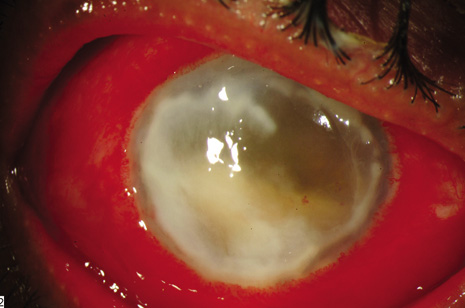

Endophthalmitis after intravitreal injection (Fig. 16) is an uncommon complication that has become the focus of attention in recent years as the use of intravitreal triamcinolone acetonide and various anti-angiogenesis medications have become available (Table 2). It is important to distinguish infectious endophthalmitis from a noninfectious pseudohypopyon caused by triamcinolone acetonide crystals (Fig. 17). Another modality, pneumatic retinopexy, is also rarely associated with the development of endophthalmitis. In the multicenter clinical trial on pneumatic retinopexy, one patient out of 103 eyes in the pneumatic retinopexy group developed endophthalmitis. A total of three endophthalmitis cases have now been reported following pneumatic retinopexy.115–117 The most common isolate is S. epidermidis and treatment approaches include standard intravitreal antibiotic injection as performed in postsurgical endophthalmitis. Strategies to reduce the risk of endophthalmitis include using a povidone-iodine ocular preparation (Fig. 18), using a lid speculum (Fig. 19), and avoiding needle contact with the lid margins and lashes (Fig. 20).

Fig. 16. Infectious endophthalmitis following intravitreal triamcinolone acetonide injection. Left: Marked conjunctival congestion, hypopyon, and prominent fibrin in the anterior chamber. Visual acuity is reduced to hand motion. Right: Higher-powered view of the anterior chamber shows marked fibrin strands in the anterior chamber.

Fig. 17. Noninfectious endophthalmitis after intravitreal triamcinolone acetonide A pseudohypopyon is created by the triamcinolone crystals in the anterior chamber. Notice the quiet conjunctiva, small, very white hypopyon, and minimal fibrin. This patient was examined on the second postinjection day as part of a routine follow-up protocol. No treatment was given and the psuedohypopyon cleared spontaneously.